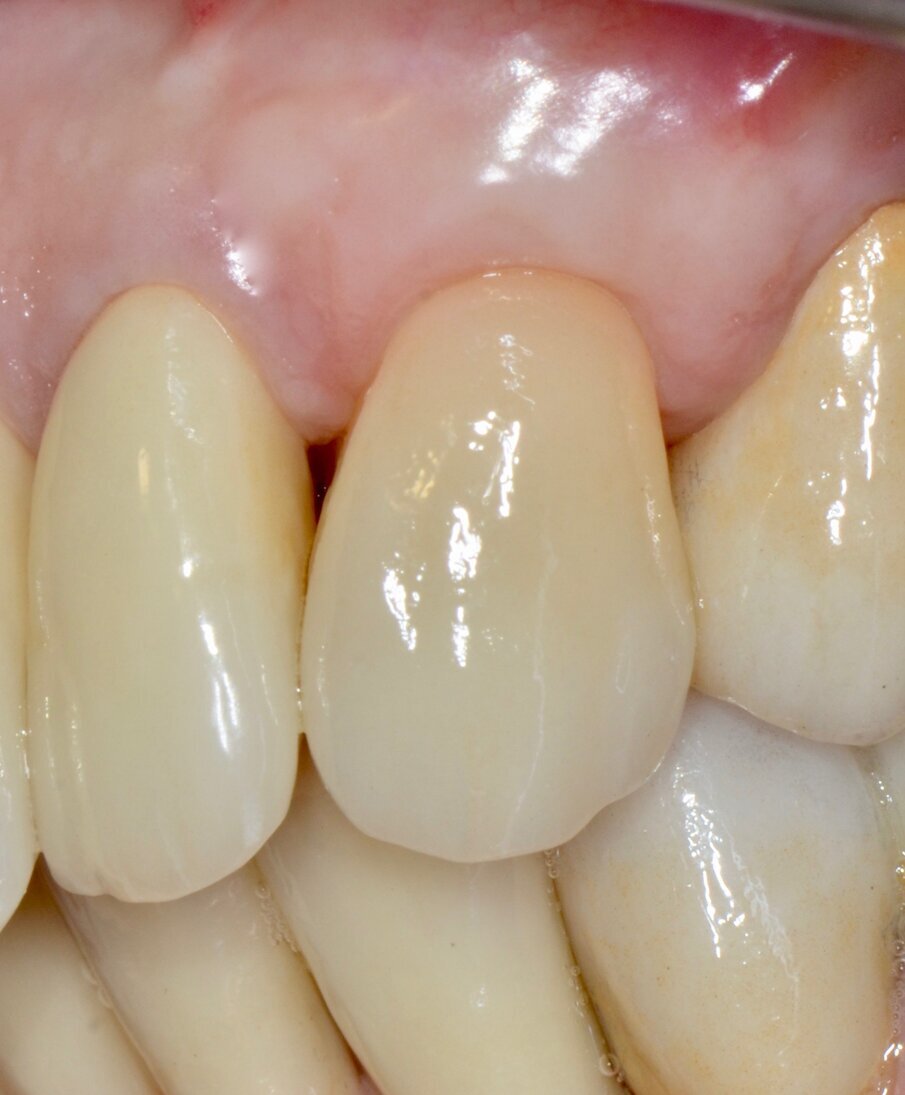

Dopo circa un mese viene eseguito un lembo a scorrimento coronale con innesto di tessuto connettivo (CAF+CTG) prelevato dal palato con la “Tecnica di Langer e Langer mod. J.Bruno” per coprire la recessione sul canino superiore sinistro e ispessire il tessuto sopra il quale verrà posizionata una faccetta in ceramica (Figg. 12-17). A due mesi dal CAF+CTG si può notare la maturazione dell’innesto con un ottimale spessore mantenuto e lo spazio guadagnato sul canino controlaterale con la ORS (Figg. 18, 19).

Valutiamo di aver raggiunto una buona simmetria delle parabole gengivali per cui si può procedere con la finalizzazione protesica (Fig. 20). I monconi sono stati preparati con una preparazione verticale per dare priorità alla robustezza dei monconi stessi nella zona cervicale (Figg. 21, 22).